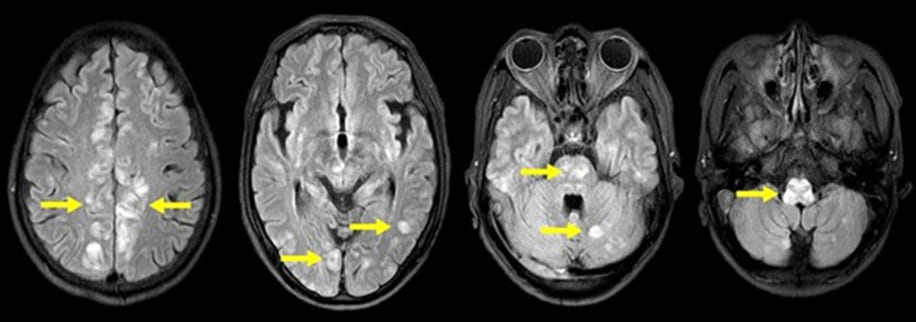

The initial brain computerized tomography (CT) scan showed no acute intracranial anomalies. Fluid-attenuated inversion recovery (FLAIR) imaging on magnetic resonance imaging (MRI) revealed bilateral multifocal high-intensity lesions in both cerebral hemispheres, along with high-intensity lesions in the brainstem and cerebellum (Figure 1). These findings, combined with neurological manifestations and severe hypertension, though atypical, raise the possibility of posterior reversible encephalopathy syndrome (PRES). Based on the laboratory results, abdomen and pelvis computed tomography (CT) scans were performed to investigate potential causes of secondary hypertension and adrenal gland abnormalities. The CT scan revealed diffuse bilateral adrenal glands enlargement (Figure 2). Furthermore, renal duplex ultrasound showed a normal hemodynamic pattern without evidence of renal artery stenosis.

Figure 1: Fluid attenuated inversion recovery (FLAIR) images on brain magnetic resonance imaging (MRI). FLAIR images reveal multifocal high-intensity lesions suggestive of vasogenic edema in the brainstem and cerebellum, accompanied by medullary bulging. Gyral swelling is evident bilaterally in the cerebral hemispheres. These findings are indicative of hypertensive encephalopathy, potentially resembling the atypical variant of posterior reversible encephalopathy syndrome (PRES). Yellow arrows highlight the identified lesions.